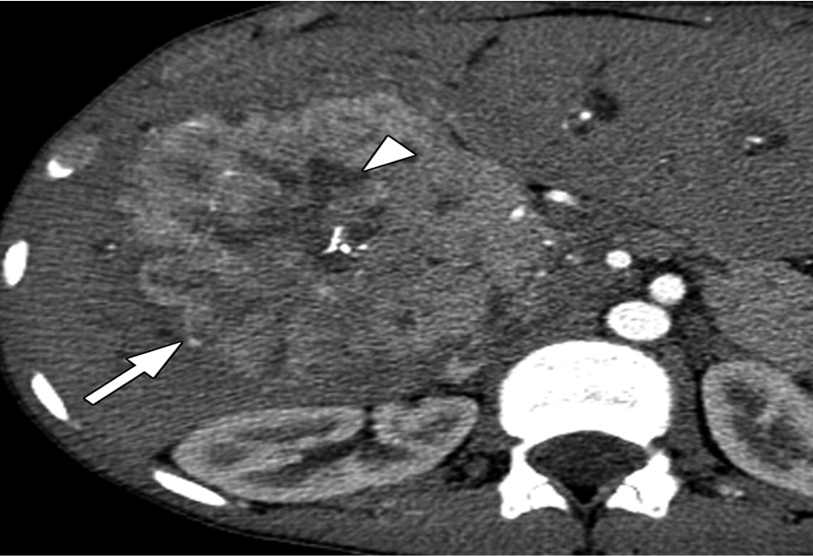

Heterogeneous mass measuring 13.3 x 11.1 x 9.7 cm, seen involving segment VIII and segment V in the right hepatic lobe, with hyperdense subsapsular hematoma at corresponding lateral hepatic surface and free intra-peritoneal hemorrhage.

A 33-year-old male patient with right hepatic haemangiosarcoma. (a) Unenhanced CT image shows a lobulate mass with an indistinct boundary in the right lobe. (b–d) Enhanced CT images of the arterial, venous, and delay phases showed a heterogeneous centripetal enhancement of the mass, and the contrast agent did not completely fill in the lesion at the end.

heterogeneous enhancement with progressive filling

irregular flame-shaped pattern

Target appearance